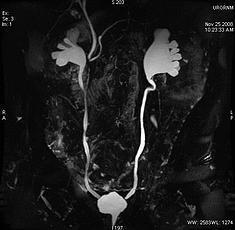

RESONANCIA NUCLEAR MAGNETICA

Mejpr estudio para ver detallada la anatomia. Se pide en paciente que no puedes ser contrastados o no se pueden irradiar. Contraindicacion en pacientes que usan implantes ferromagneticos. T1 es bueno para ver anatomia: blanco: grasa, hemorragia, sustancia blanca. Gris; sustancia gris, higado, bazo, pancreas, riñon, musuclo, lesines con agua, Negro: orina, quistes, tendones, vasos, aire T2 es bueno para ver patologia. Blanco: orina, quistes, tumores, riñon, bazo, agua libre, LCR. Gris; sustancia gris, grasa. Negro: pancreas, higado, musculo, hueso cortical, tendones, aire, vasos. Como los cambiospatologicos son inflamatorios o tumorales, cambios de edema(aumento de agua). En T2 el agua es blanca por lo que las lesiones se ven hiperintensas en T2.

La uro resonacnia no sirve para ver piedras comparado con el uro TC Cancer de vejiga: leccion para su etapificacion ya que permite ver la pared vesical. Cancer de prostata; Score PIRADS, compromiso pared prostata, de vesiculas seminales.